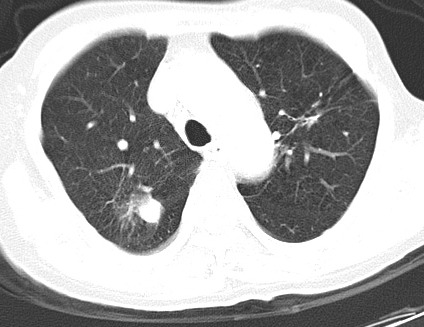

以下是引用hhcckk在2007-3-2 14:51:00的发言:[br]考虑结核球可能性大,依据[br]1病灶在下叶背段,结核的好发部位[br]2病灶内有大量的钙化,纵隔内有大量的淋巴结钙化[br]3重要的是半年前与现在相比无变化,假如是肿瘤的话不会这么‘善良’[br]4病灶周围卫星灶不明显,病灶有毛刺,胸膜凹陷,肿瘤不能完全排除,有条件的话最好做个活检

以下是引用liuyue在2007-3-2 17:15:00的发言:[br]1位置:右上叶后段[br]2性质:大分叶、粗长毛刺、条状斑片状钙化、纵隔多发淋巴结钙化,无强化,故考虑:肺结核灶(陈旧)